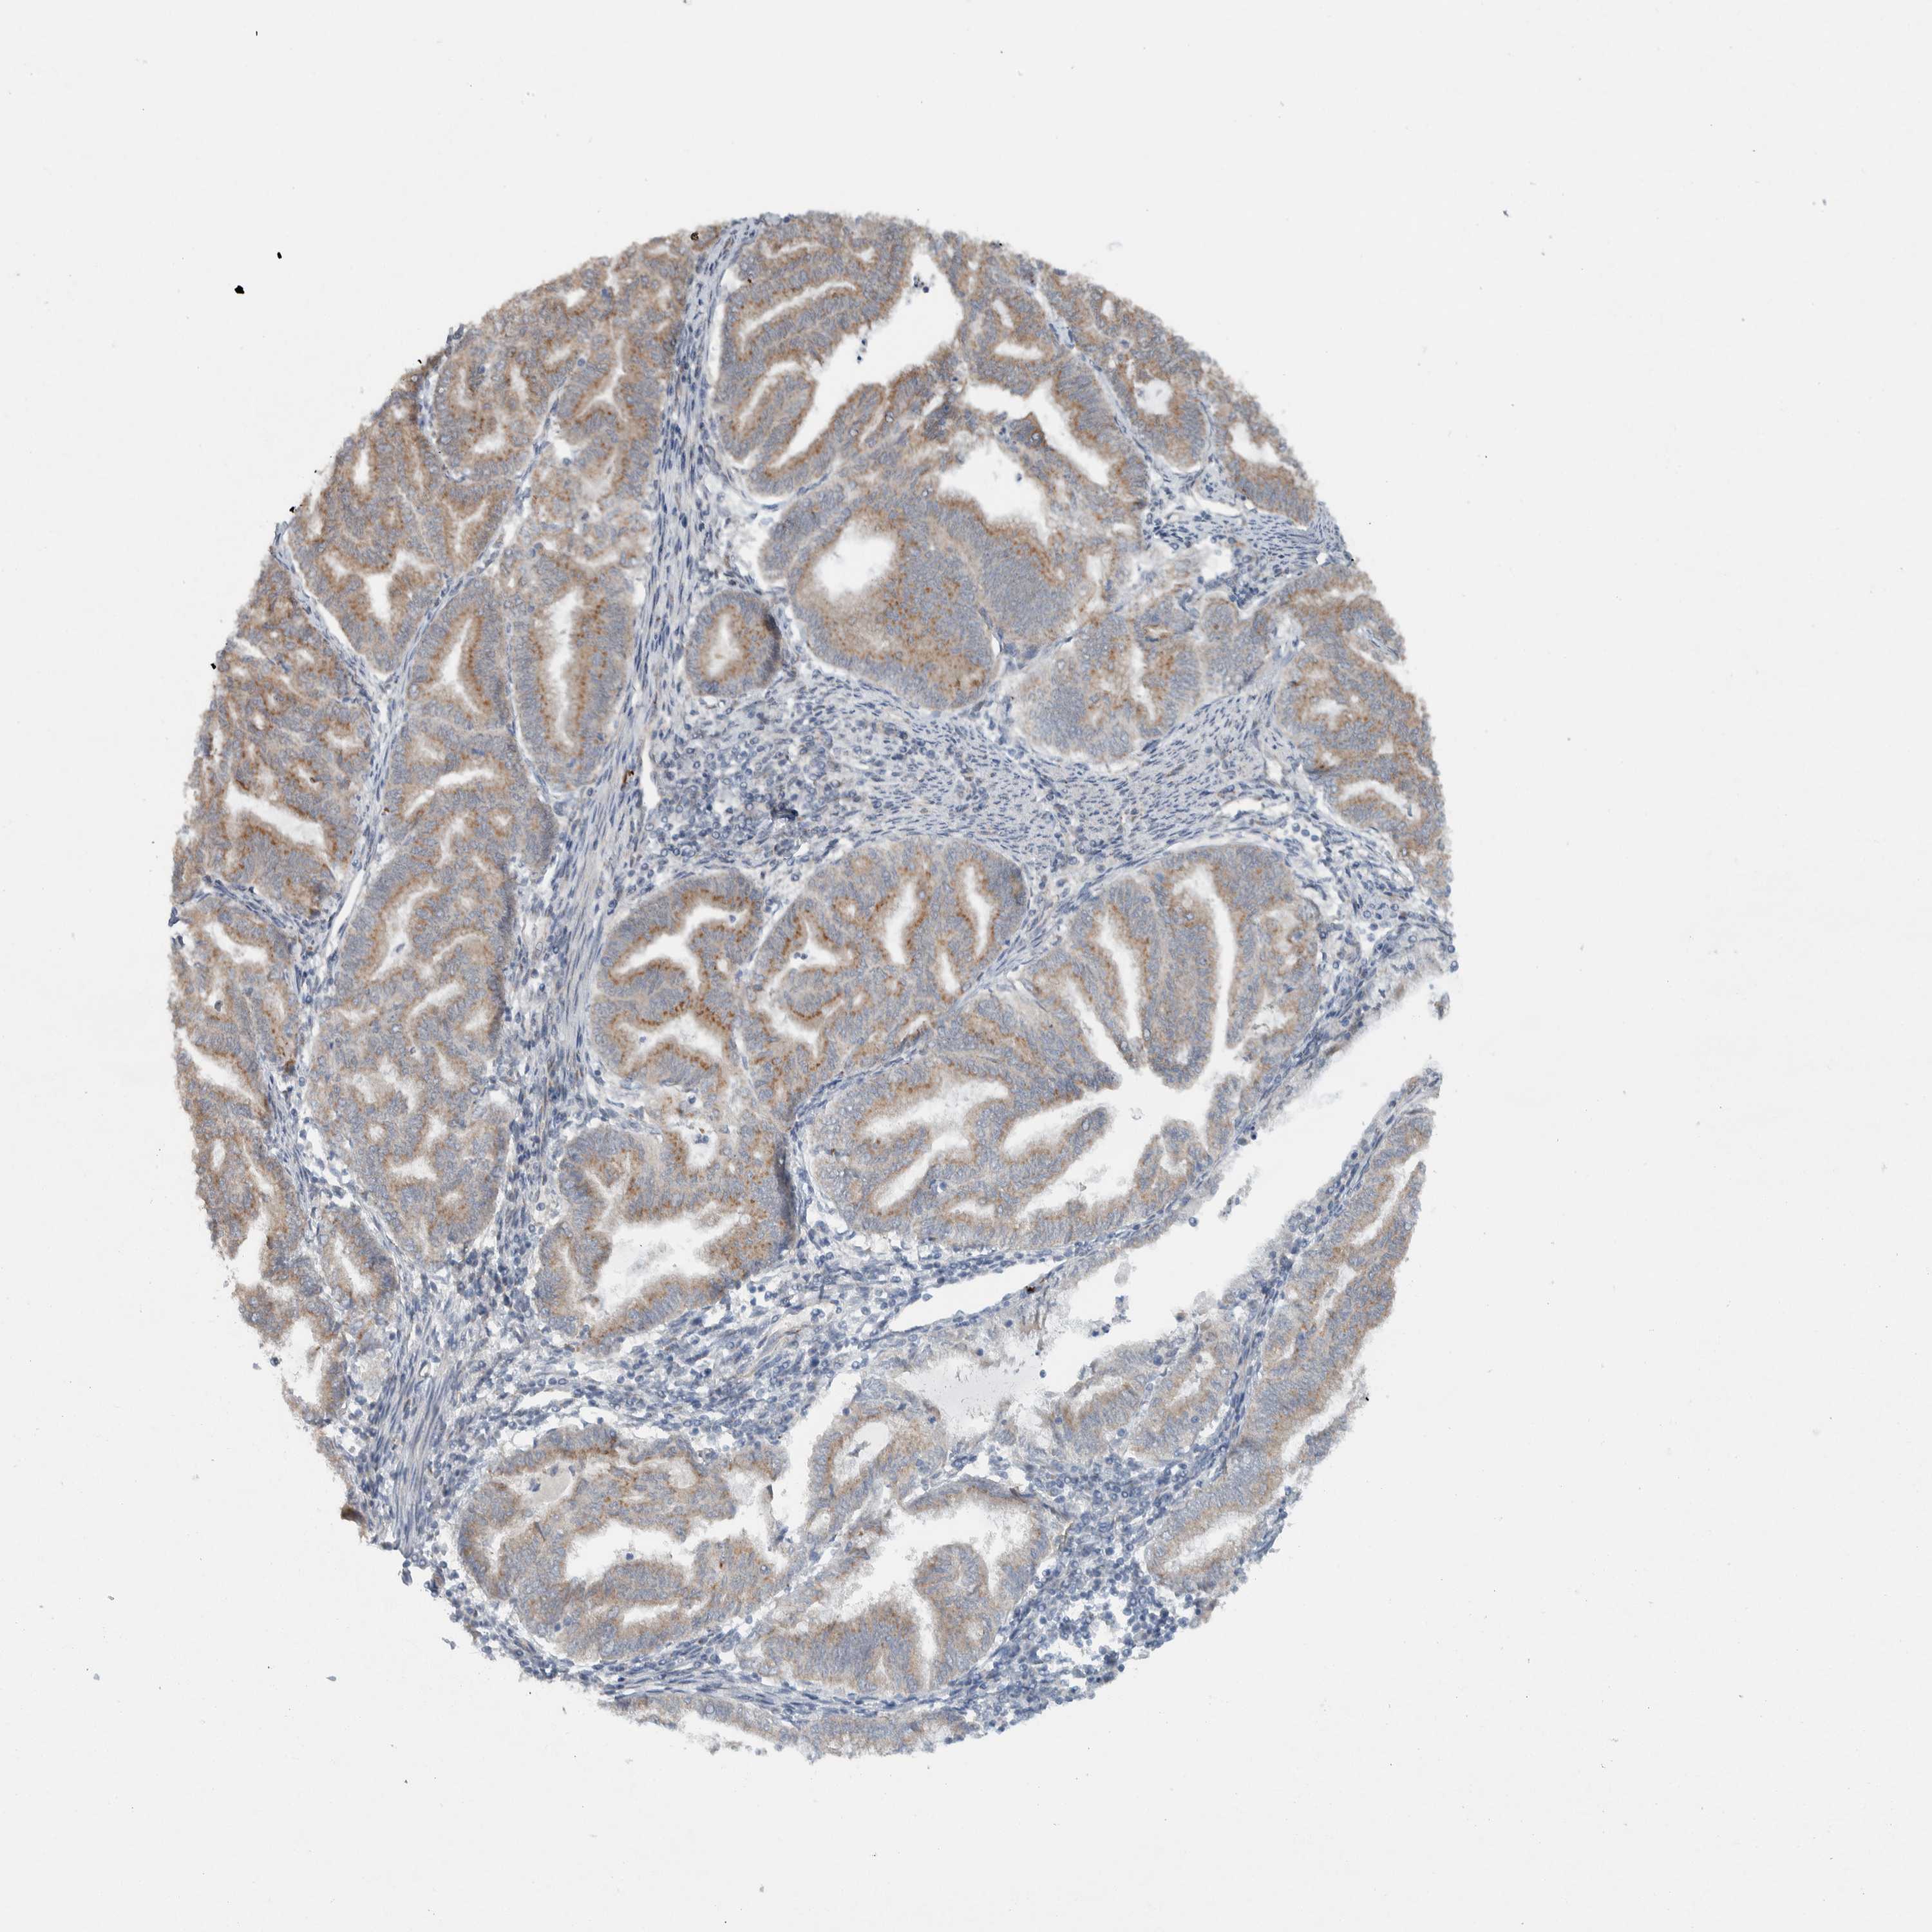

ENDOMETRIAL CANCER - Protein expressioni

A mouse-over function shows sample information and annotation data. Click on an image to view it in a full screen mode. Samples can be filtered based on level of antibody staining by selecting one or several of the following categories: high, medium, low and not detected. The assay and annotation is described here.

Note that samples used for immunohistochemistry by the Human Protein Atlas do not correspond to samples in the TCGA dataset.

Antibody stainingi

Antibody staining in the annotated cell types in the current human tissue is reported as not detected, low, medium, or high, based on conventional immunohistochemistry profiling in selected tissues. This score is based on the combination of the staining intensity and fraction of stained cells.

Each image is clickable and will lead to virtual microscopy that enables deeper exploration of all samples and also displays staining intensity scores, fraction scores and subcellular localization as well as patient and tissue information for each sample.

Antibody HPA024093

Staining

High

Medium

Low

Not detected

Intensity

Strong

Moderate

Weak

Negative

Quantity

>75%

75%-25%

<25%

None

Location

Nuclear

Cytoplasmic/membranous

Cytoplasmic/membranous,nuclear

Adenocarcinoma, NOS